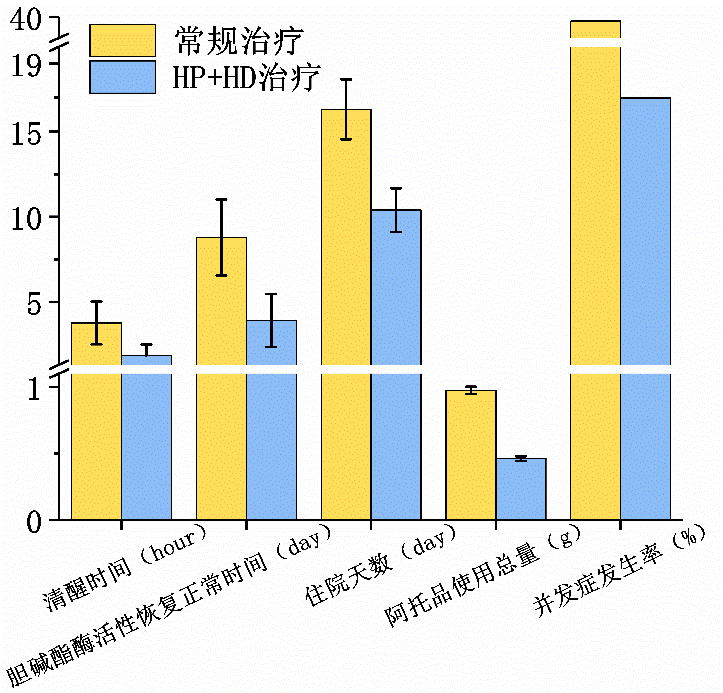

有機磷農藥是全球使用最為廣泛、用量最大的殺蟲劑之一。常見的有機磷農藥包括敵百蟲、敵敵畏、氧化樂果等,其揮發性強,在使用期間容易透過皮膚或經由呼吸道進入人體而誘發中毒。重度有機磷中毒具有并發癥多、病死率高、預后差的特點,故中毒后予以積極的救治成為促使患者轉危為安的重要保障。有機磷進入人體后會與膽堿酯酶結合,使得機體內聚集大量乙酰膽堿,造成交感、副交感神經等過度興奮,從而導致心肌細胞受損,而血液灌流聯合血液透析(HD)治療方案能促進患者病癥消退,縮短膽堿酯酶活性恢復時間,利于促進康復進程。[7]

圖4 有機磷中毒患者不同治療方式后的恢復情況